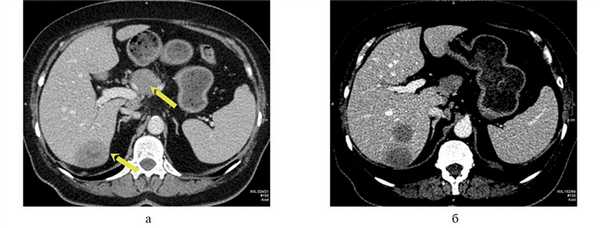

КТ органов брюшной полости с внутривенным контрастированием (23.05.2016): печень обычно расположена, краниокаудальный размер правой доли до 159 мм. В правой доле печени определяются единичные гиповаскулярные образования округлой формы, имеющие зону кистозной плотности в центральных отделах, в S7 до 24 мм в диаметре, на границе S7/6 деформирующее внешний контур печени образование размером до 44×32 мм, в S6 — до 30 мм. С нижней поверхностью S4, рядом с ямкой желчного пузыря, сливается образование, схожей структуры, расположенное преимущественно за пределами контура печени, округлой формы, размером до 27×12×20 мм, внутри- и внепеченочные желчные протоки не расширены. Желчный пузырь не увеличен, без рентгеноконтрастных включений. Селезенка не увеличена, структура однородная. В перешейке поджелудочной железы определяется гиповаскулярное образование с экзофитным ростом, неправильной округлой формы, размерами до 30×32×35 мм. Образование контактирует с поверхностью хвостатой доли печени, прилежит к сосудам портального бассейна в области конфлюэнса, а также по поверхности образование огибают общая печеночная артерия, гастродуоденальная артерия и собственная печеночная артерия, кровоснабжающая левую долю печени (правая доля печени кровоснабжается собственной печеночной артерией, идущей от верхней брыжеечной артерии). Остальные отделы поджелудочной железы с признаками атрофии. Вирсунгов проток не расширен. Прилежащая передняя парапанкреатическая клетчатка рядом с перешейком железы тяжистая, в ней определяются единичные лимфатические узлы размером до 6 мм. Надпочечники типичной Y-образной формы, правый надпочечник без объемных образований, в латеральной ножке левого надпочечника определяется образование размерами 12×11 мм, плотностью при нативном исследовании до 22 HU, накапливающее контрастный препарат в артериальную фазу до 97 HU и сбрасывающее его к отсроченной фазе до 48 HU. Почки обычно расположены, кортикомедуллярная дифференцировка сохранена. В синусах обеих почек определяются парапельвикальные кисты размерами: справа — до 32×16 мм, слева — до 25×17 мм. В нижнем сегменте левой почки также определяется киста размером до 39×32 мм. Чашечно-лоханочная система не расширена, выделительная функция синхронна, своевременна. Сосудистые ножки дифференцированы. В малом сальнике немногочисленные лимфатические узлы размером до 7 мм каждый, интрааортокавальные и по ходу почечных ножек справа размерами до 14 мм, в печеночно-двенадцатиперстной связке узлы максимальным размером до 28×16 мм. Выпота в брюшной полости нет. Атеросклеротические изменения аорты и подвздошных сосудов. Заключение (рис. 1, рис. 2):опухоль поджелудочной железы. Метастатическое поражение печени. Абдоминальная и забрюшинная лимфаденопатия. Образование в левом надпочечнике также вероятно метастатического характера. Кисты почек.

Рис. 1. КТ брюшной полости с внутривенным контрастированием. а — поперечный срез, стрелками указаны объемные образования поджелудочной железы и печени; б — поперечный срез, очаговые образования правой доли печени.

Рис. 2. КТ брюшной полости с внутривенным контрастированием (сагиттальный срез, стрелкой указано образование поджелудочной железы).